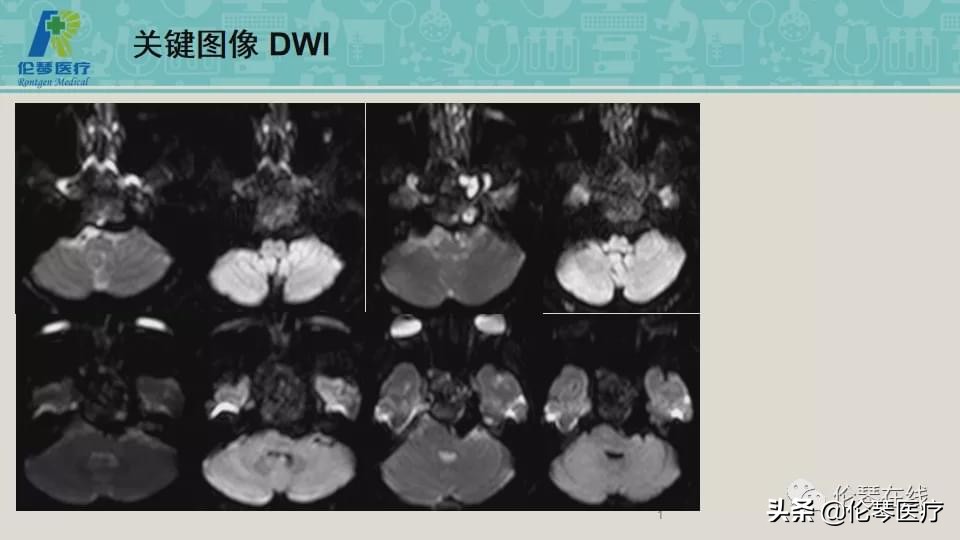

性别:男

年龄:21岁

主诉:头痛,双眼内收、外展受限8个月,加重2月

检查:CT扫描(影像图像见下方)